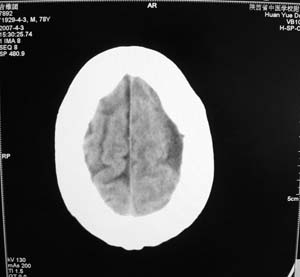

以下是引用star--868在2007-6-15 20:54:00的发言:[br]1.左侧额颞顶部亚急性硬膜下血肿并继续出血 双侧额颞顶部硬膜下积液;[br]2.左颞枕叶、左基底节区脑软化-左侧大脑中动脉栓塞;[br]双侧额颞顶部硬膜下积液应和治疗期间应用高渗脱水剂相鉴别:停用甘露醇后硬膜下积液会逐渐吸收减少,而单纯硬膜下积液无此改变和/或逐渐增多。

以下是引用老爱克斯新网客在2007-6-15 20:40:00的发言:[br]1左侧颞叶软化灶,2双侧硬膜下水瘤,3左册硬膜下血肿(多次少量出血),

以下是引用还珠格格在2007-6-16 7:07:00的发言:[br]支持.左侧额颞顶部亚急性硬膜下血肿并继续出血 双侧额颞顶部硬膜下积液;[br]2.左颞枕叶、左基底节区脑软化-左侧大脑中动脉栓塞;